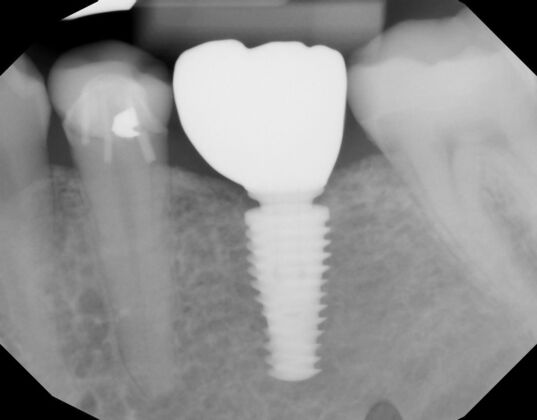

Patient lost lower first molars and required two lower implants with two lower screw retained crowns